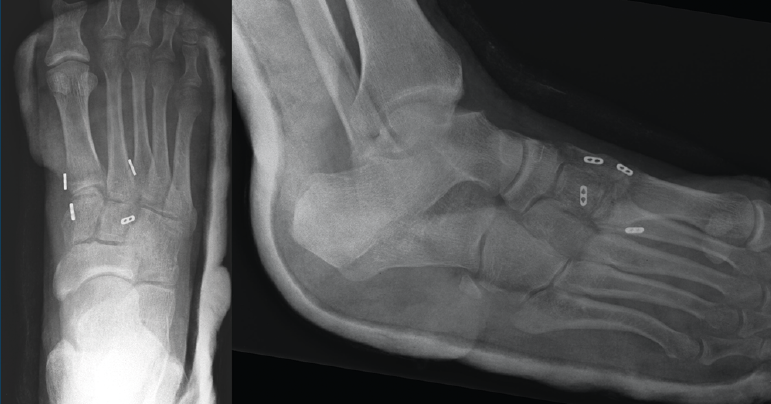

Se realiza la intervención quirúrgica a las 8 semanas con reducción abierta mediante abordaje dorsomedial confirmando la inestabilidad articular y realizando una estabilización con sutura intraósea con botón de C1-M2. Se comprueba que aún persistía cierta inestabilidad en el plano frontal, por lo que se decide poner otro dispositivo de C2 a M1. Se inmoviliza con una férula suropédica y se indica descarga (Figura 2).

Figura 2. Caso 1. Resultados radiográficos posquirúrgicos.